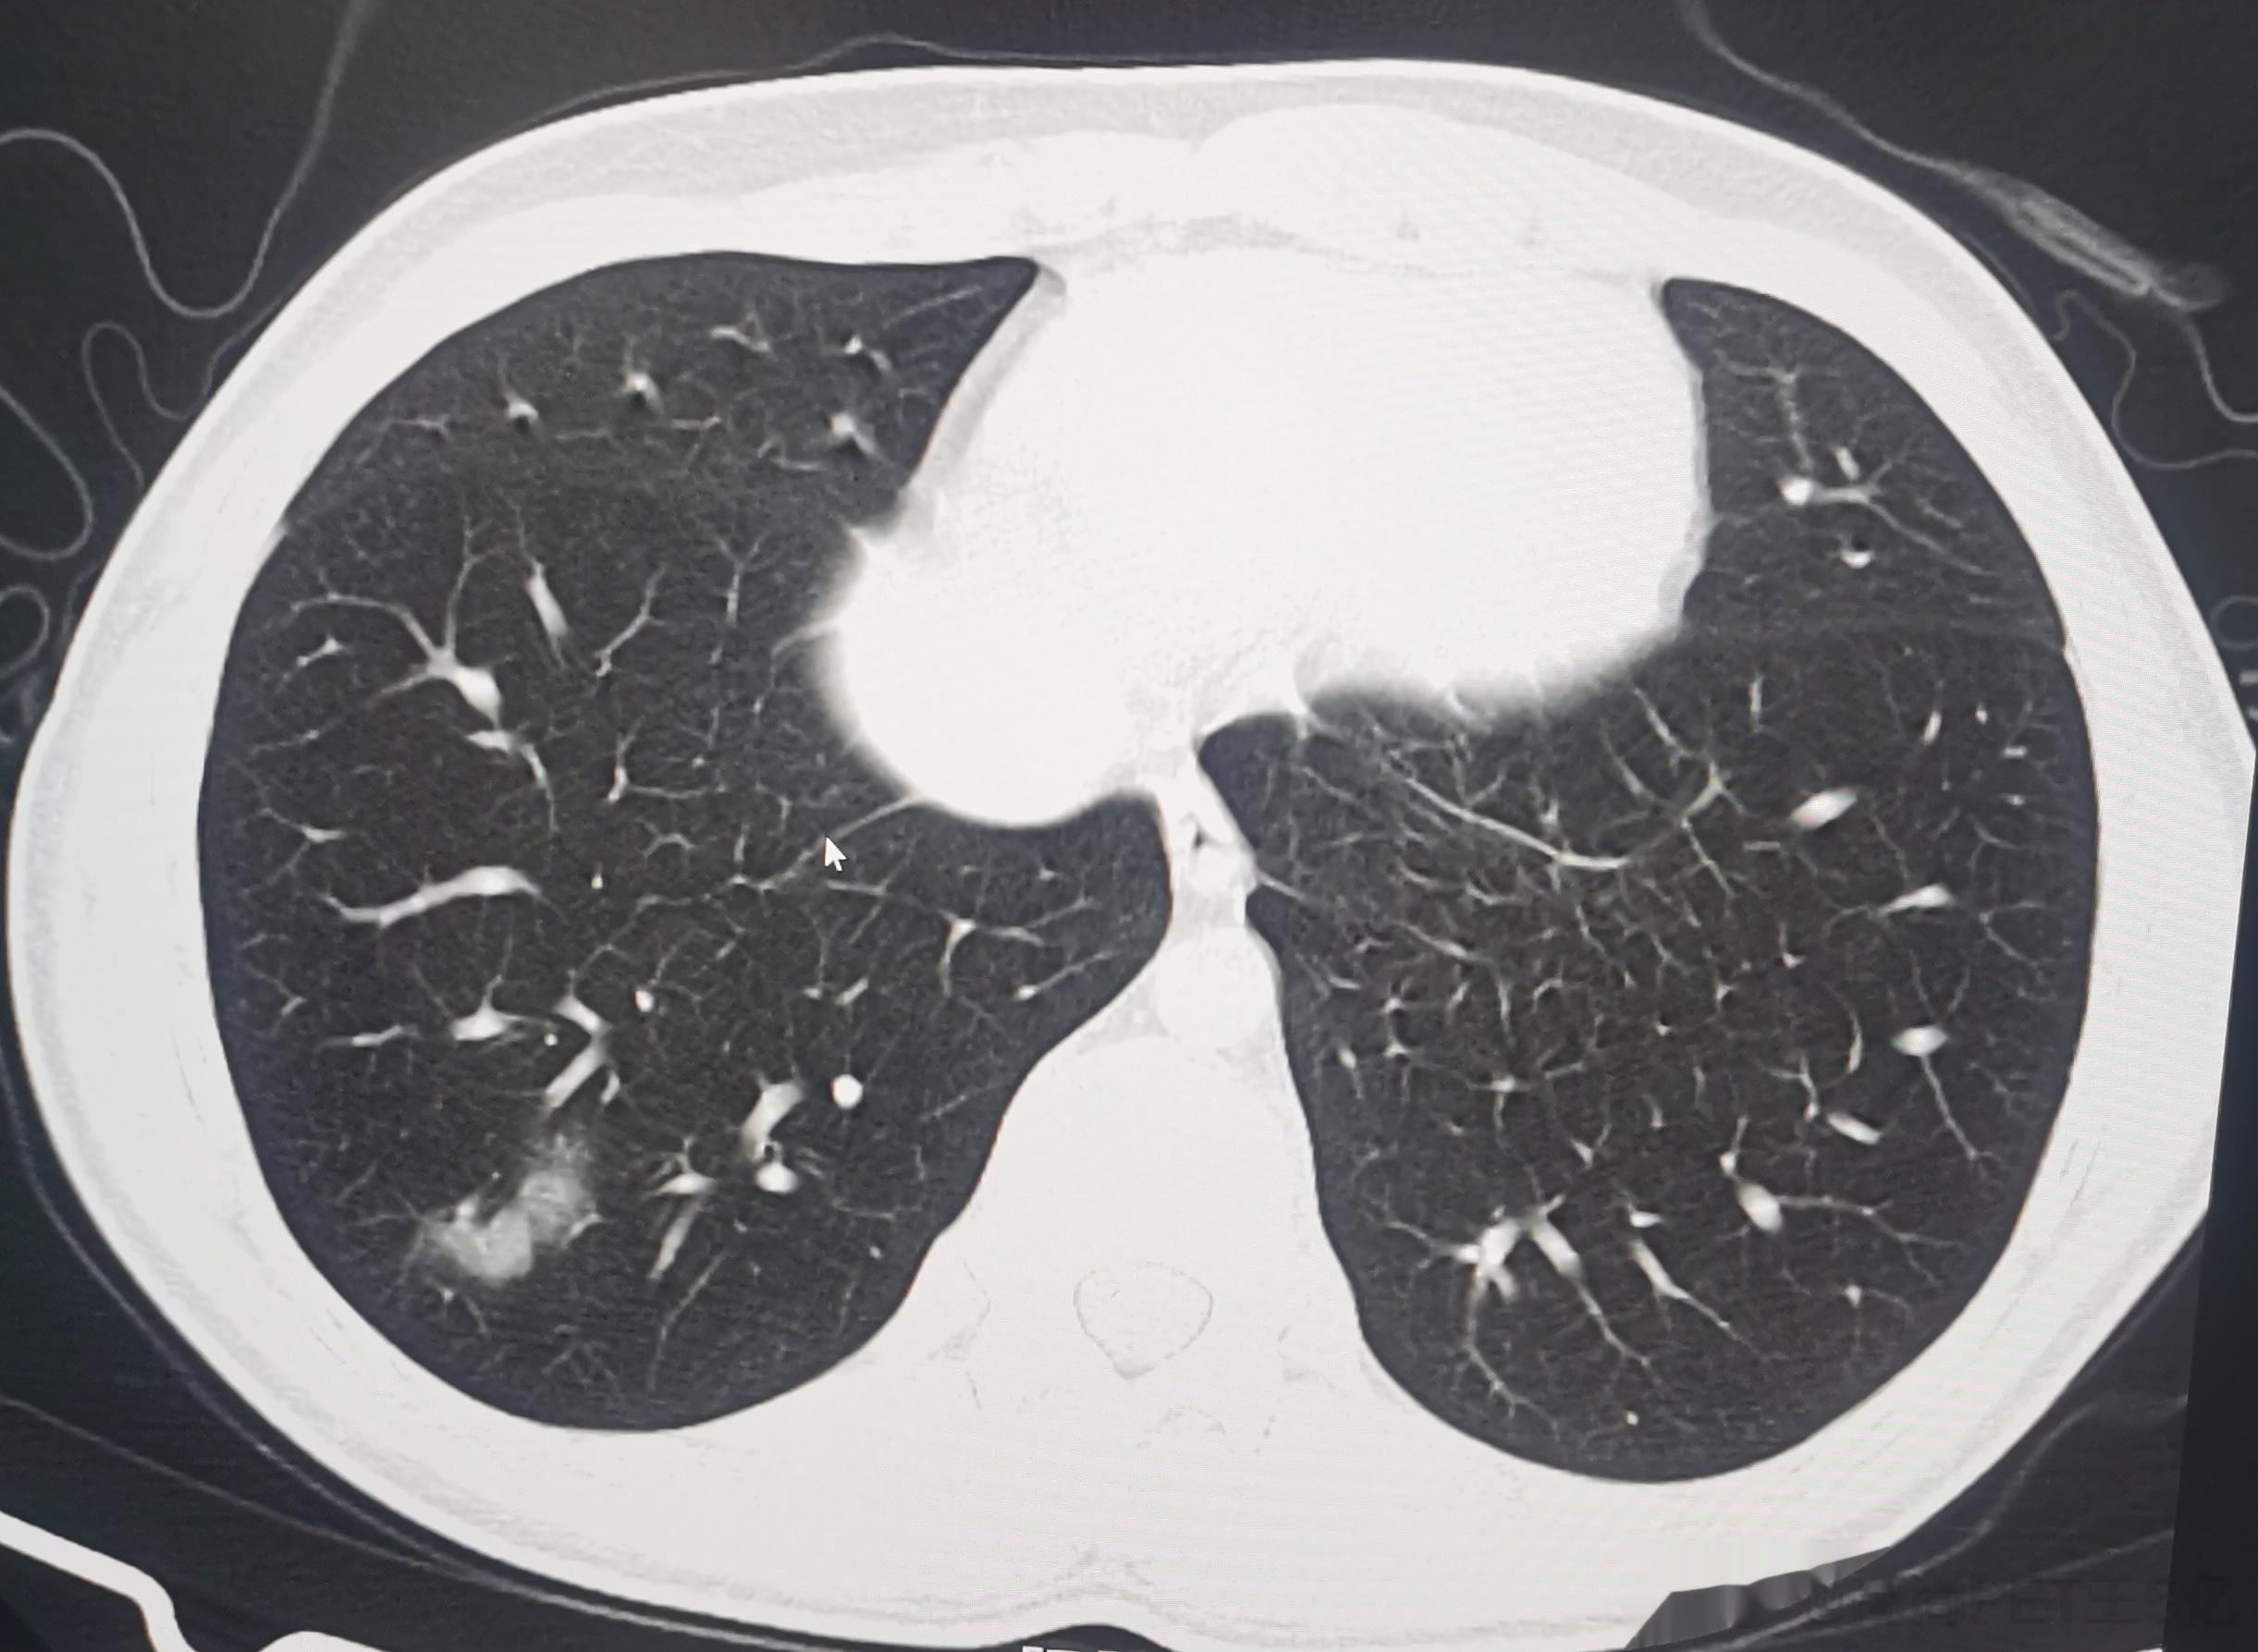

今日我们高尚影像中心新冠肺炎筛查病人是108例,其中28例有轻度新冠肺炎影像表现,检出率接近26%,最最小14岁(下面第一排CT图像),最大年龄是87岁(下面第二排CT图像),大部分人的年龄超过60例。由此可以看出,新冠病毒肺炎可能会累及各个年龄段,但主要还是60岁以上老年人群。如果新冠感染超过2周咳嗽症状还不减轻者,最好做一个胸部CT判断有无新冠病毒肺炎,这对于决策治疗方案及预测治疗效果都很关键。#老年人感染新冠后小心肺炎##感染新冠都要做CT吗#

今日我们高尚影像中心新冠肺炎筛查病人是108例,其中28例有轻度新冠肺炎影像表现,检出率接近26%,最最小14岁(下面第一排CT图像),最大年龄是87岁(下面第二排CT图像),大部分人的年龄超过60例。由此可以看出,新冠病毒肺炎可能会累及各个年龄段,但主要还是60岁以上老年人群。如果新冠感染超过2周咳嗽症状还不减轻者,最好做一个胸部CT判断有无新冠病毒肺炎,这对于决策治疗方案及预测治疗效果都很关键。#老年人感染新冠后小心肺炎##感染新冠都要做CT吗#